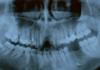

GITARIST Опубликовано 31 марта, 2010 Поделиться Опубликовано 31 марта, 2010 (изменено) Здравствуйте подскажите пожалуйста, сделали резекцию верхушки корня верхнего зуба, прошло 5 месяцев, неделю назад воспалилось, образовался шарик, но боли не было. Пропил антибиотики Сумамед и Найз. Опухоль сошла, но покраснение осталось. Есть ли положительная динамика и можно ли протезировать? Верхний зуб слева если смотреть на фото запломбированный. Заранее спасибо! Изменено 31 марта, 2010 пользователем GITARIST Ссылка на комментарий

r3yand Опубликовано 31 марта, 2010 Поделиться Опубликовано 31 марта, 2010 снимок конечно не очень (по качеству), но видно еще небольшое периапикальное разрежение.о динамике говорить без снимка до операции невозможно.насчет протезирования я бы сначала сделал пластмассовую коронку на пол года, проследить за динамикой (если есть сомнения насчет того зуба). Ссылка на комментарий